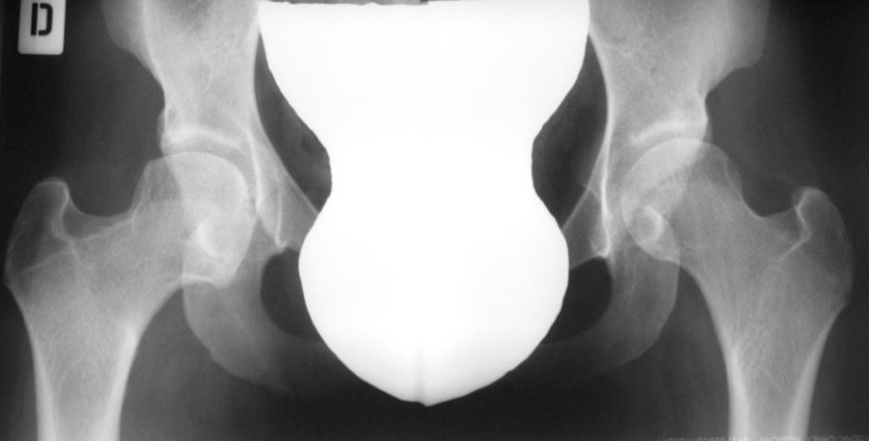

L’esame ecografico è stato introdotto negli anni 80 da Graf che ha proposto una classificazione in quattro tipi per valutare condizioni di immaturità dell’anca (Tipo II) e condizioni più gravi come la sublussazione (Tipo III) e la lussazione franca (Tipo IV) 5. Il metodo è basato sulla valutazione dell’entità di due angoli: l’angolo α formato dalla linea di base che è rappresentata dalla continuazione verso il basso del profilo laterale dell’ala iliaca e la linea del tetto osseo mentre l’angolo β è formato sempre dalla linea di base e la linea del tetto cartilagineo. La radiografia dell’anca può essere attualmente utilizzata con lo scopo di confermare la diagnosi dopo i 4-6 mesi di vita. Nei casi di displasia è presente la caratteristica triade di Putti caratterizzata dalla sfuggenza del tetto acetabolare, dal ritardo di comparsa o dall’ipoplasia del nucleo di ossificazione della testa femorale che rappresentano segni di ritardo dell’ossificazione acetabolare e dall’allontanamento/risalita dell’epifisi prossimale del femore che viene valutata attraverso interruzione dell’ogiva o arco di Shenton. Tale ogiva è formata dal margine mediale della metafisi femorale che, in condizioni di normalità, si continua con il margine inferiore della branca ileo-pubica (Fig. 5).